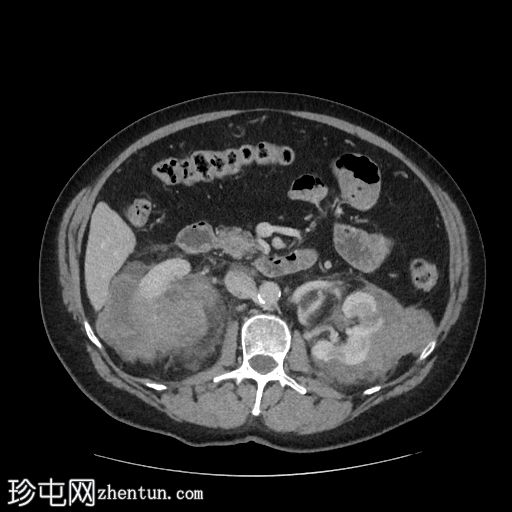

轴位增强扫描(门静脉期)

右肾可见不规则分叶状低密度浸润性病变,超出肾包膜,并与右肝下叶相邻。

左肾可见弥漫性浸润性病变,以上极为中心。左肾浸润性病变与胰尾相邻,胰尾可能受累,表现为胰腺后缘不规则、脂肪间隙消失。此外,浸润性病变与左侧肾上腺外侧肢相邻。

脾脏下极可见一密度不明、呈分叶状/浸润性改变的肿块。